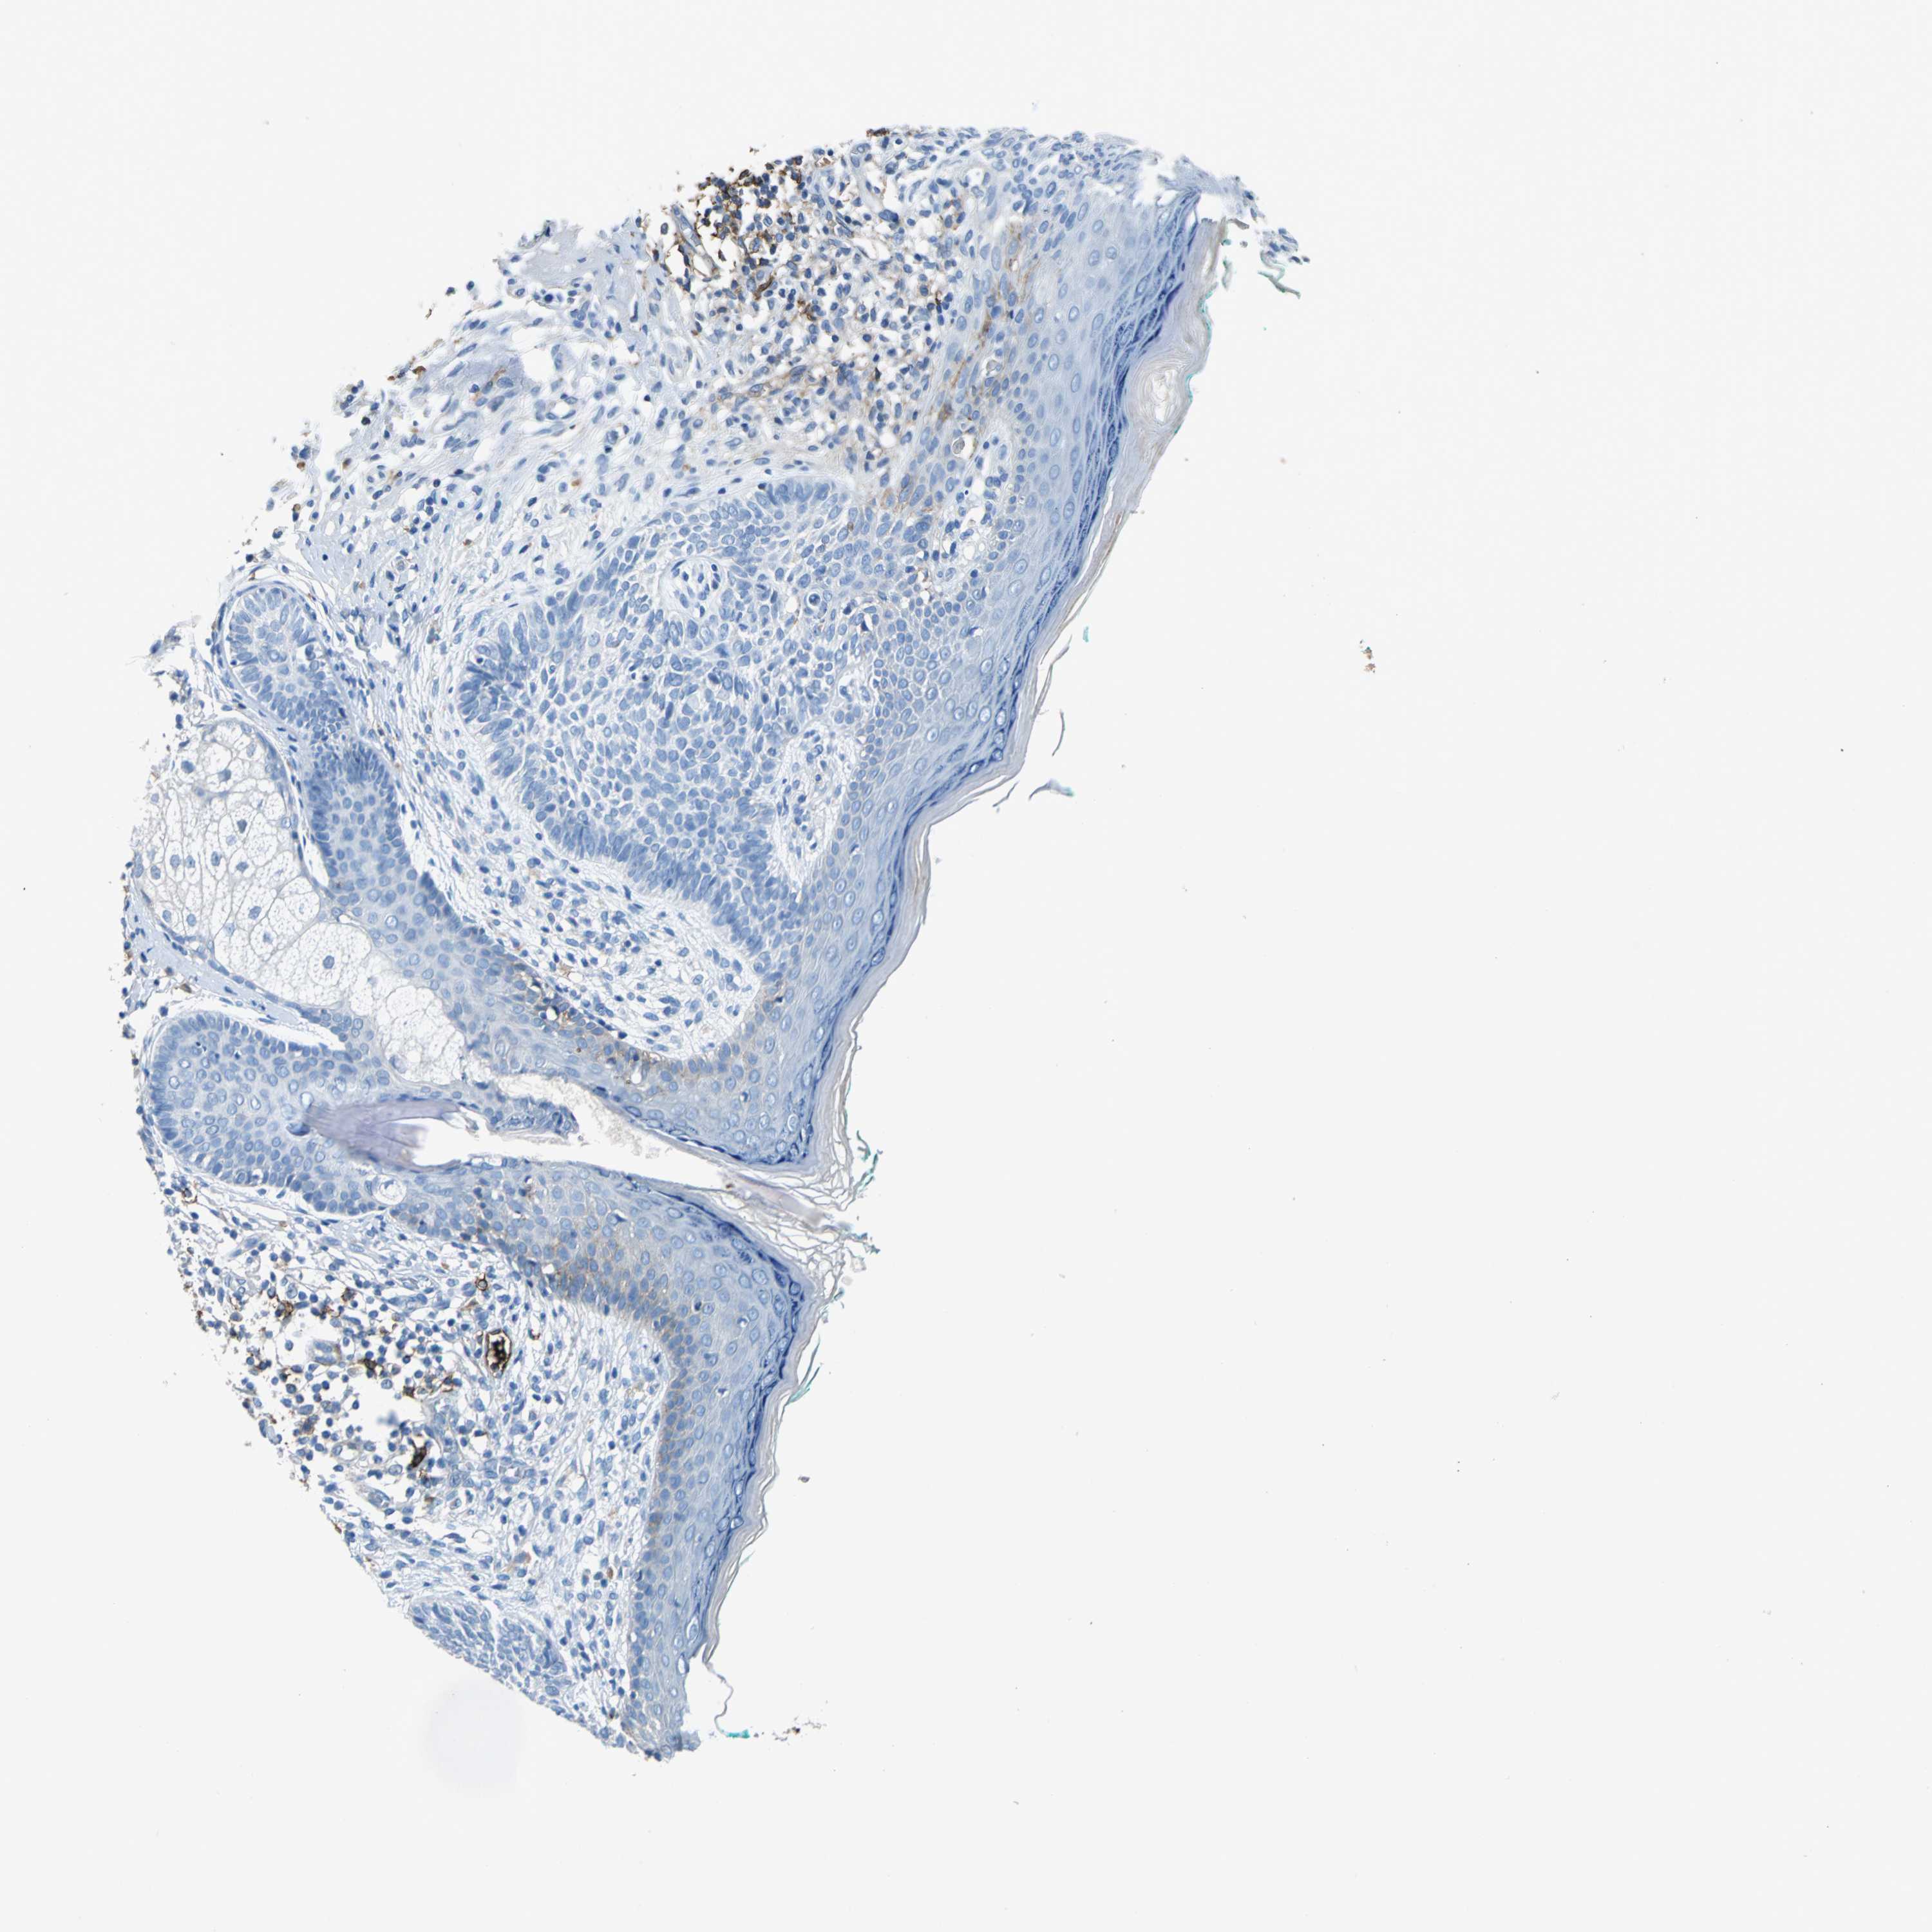

SKIN CANCER - Protein expressioni

A mouse-over function shows sample information and annotation data. Click on an image to view it in a full screen mode. Samples can be filtered based on level of antibody staining by selecting one or several of the following categories: high, medium, low and not detected. The assay and annotation is described here.

Antibody stainingi

Antibody staining in the annotated cell types in the current human tissue is reported as not detected, low, medium, or high, based on conventional immunohistochemistry profiling in selected tissues. This score is based on the combination of the staining intensity and fraction of stained cells.

Each image is clickable and will lead to virtual microscopy that enables deeper exploration of all samples and also displays staining intensity scores, fraction scores and subcellular localization as well as patient and tissue information for each sample.

Antibody HPA005985

Staining

High

Medium

Low

Not detected

Intensity

Strong

Moderate

Weak

Negative

Quantity

>75%

75%-25%

<25%

None

Location

Nuclear

Cytoplasmic/membranous

Cytoplasmic/membranous,nuclear

Basal cell carcinoma